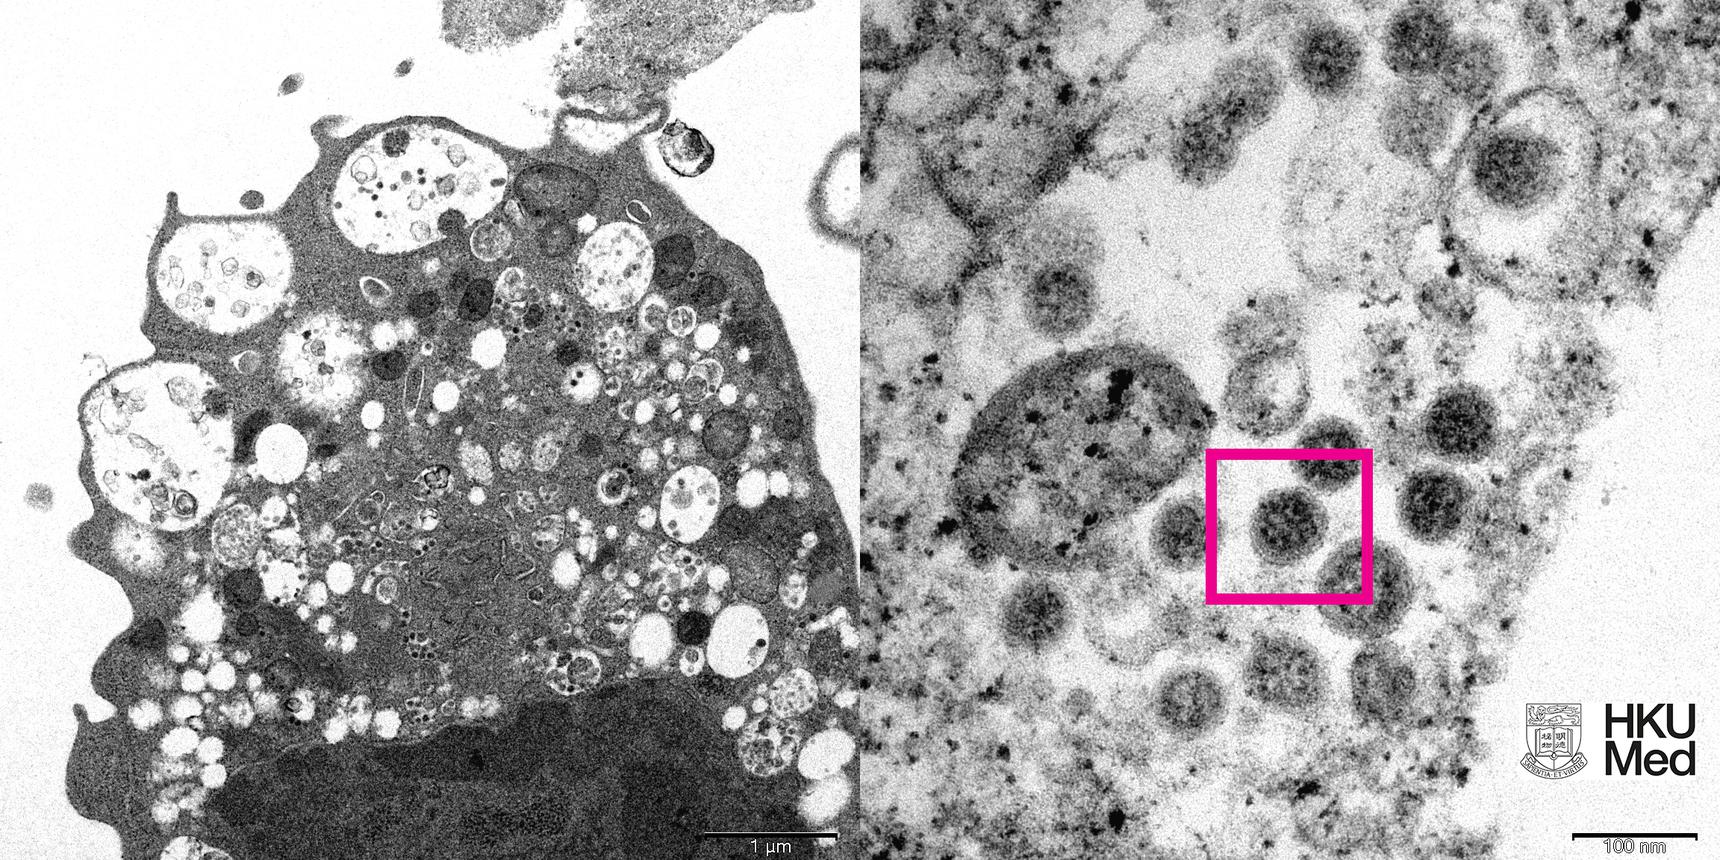

Исследователям из Университета Гонконга удалось сделать фотографию нового нашумевшего штамма коронавируса — омикрон. Об этом сообщает Ferra.ru со ссылкой на официальный сайт научной организации.

Для того, чтобы сделать снимок, ученые исследовали клетки почки обезьяны, которая была заражена омикрон-штаммом. Почка сильно повредилась, набухла, а внутри содержались вирусные частицы. При сильном увеличении им удалось даже разглядеть скопления характерных сферообразных объектов с шипами в форме короны на их поверхности.